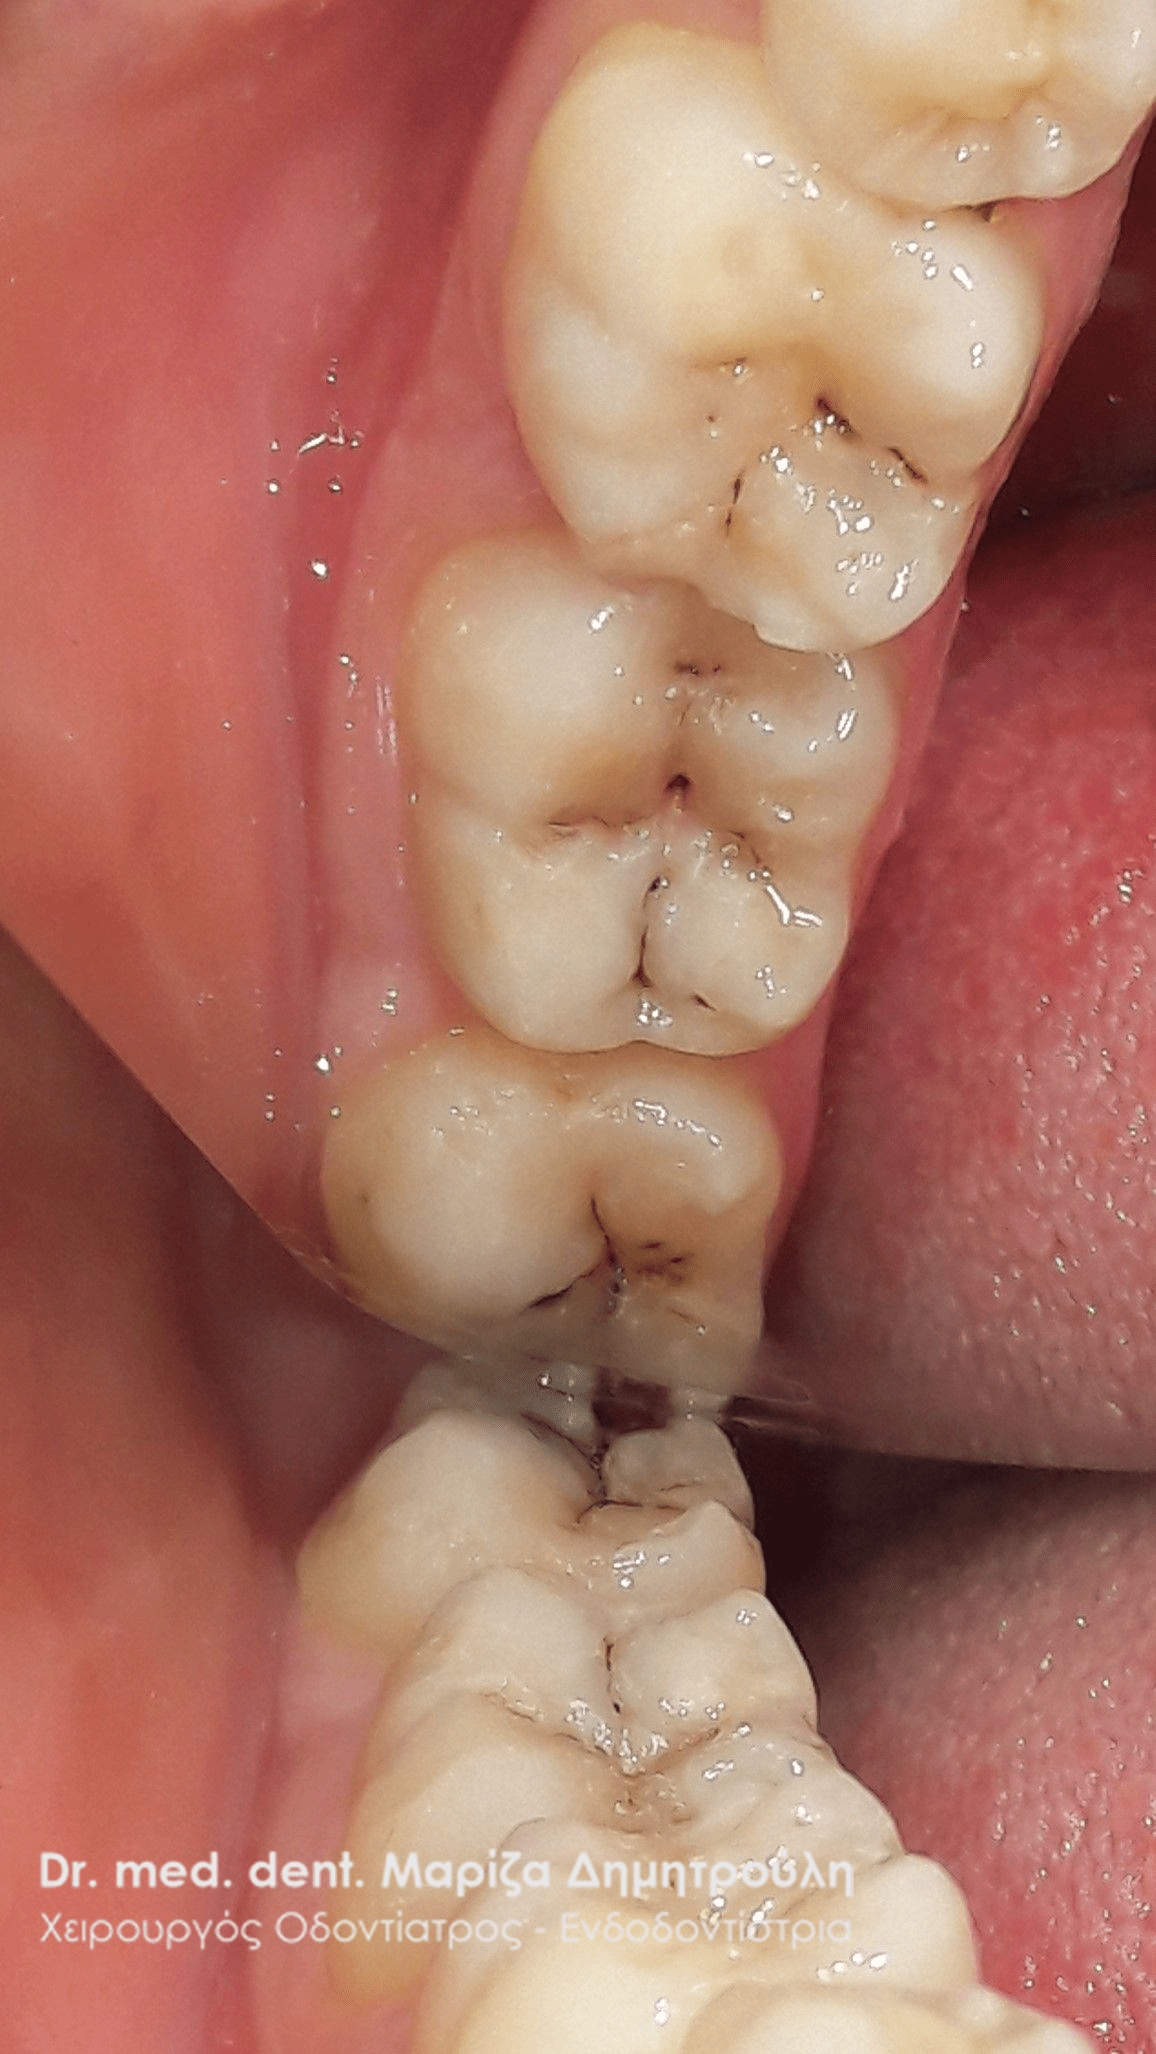

Αρχική εικόνα κάτω αριστερών γομφίων

Εικόνα 1ου κάτω αριστερού γομφίου μετά τη διάνοιξη του

Τελική εικόνα 1ου κάτω αριστερού γομφίου

Τελική εικόνα 2ου κάτω αριστερού γομφίου